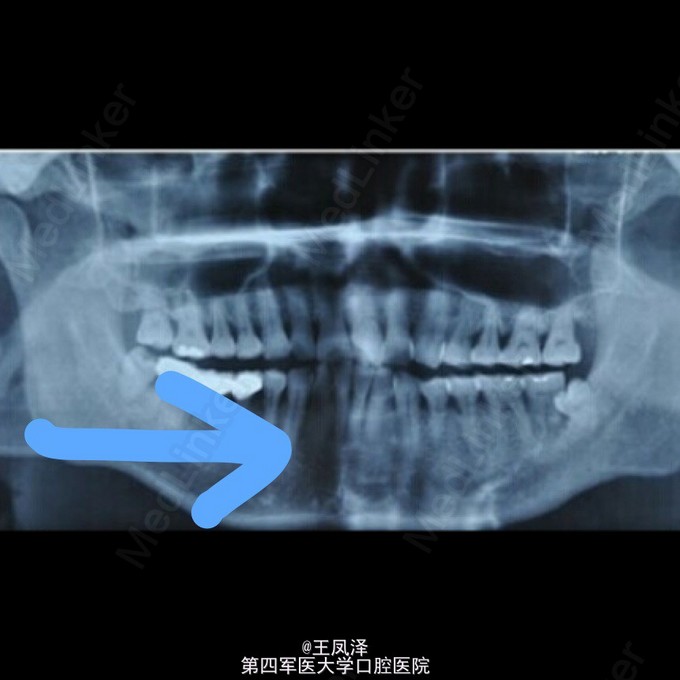

罕见下前牙根尖周炎引起颏部皮肤窦道一例

患者,男,因颏部正中皮肤窦道反复排脓就诊